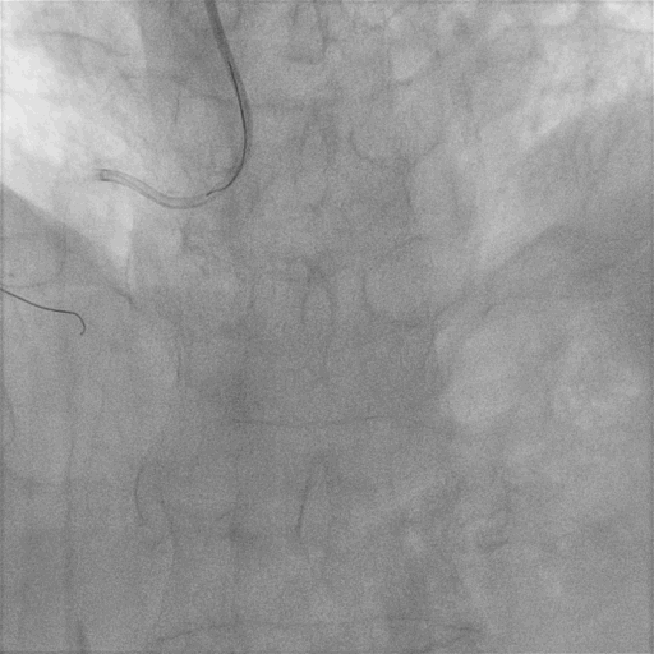

反复多体位造影提示:病变部位残余狭窄小于30%,未见明显夹层及撕裂,TiMi血流III级;